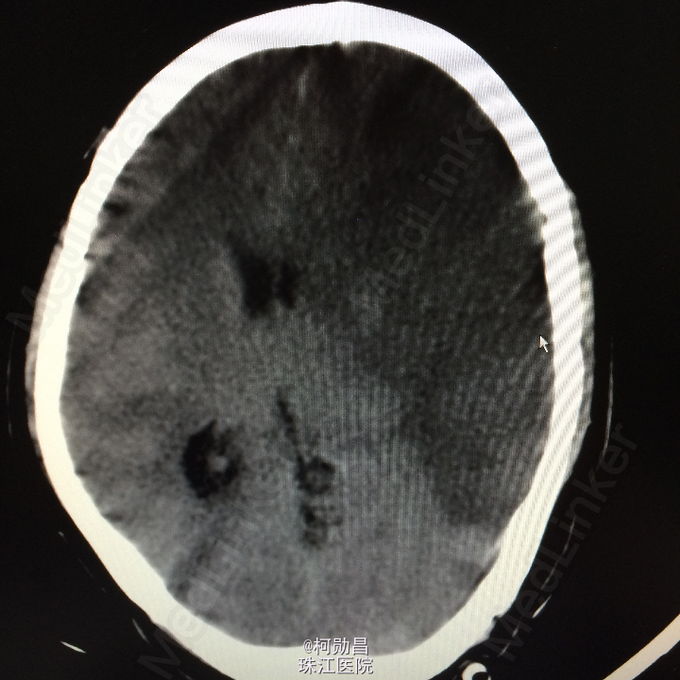

主诉:突发言语不能伴右侧肢体无力1天余 病史:患者于1天前无明显诱因突发言语不能,伴右侧肢体无力,表现为右侧肢体不能自主活动,无头痛头晕,无恶心呕吐,无肢体麻木、四肢抽搐、意识不清等症状。于当地医院就诊,查头颅CT提示:未见异常,予对症支持治疗,症状无好转。半天前患者症状加重,出现神志不清,呈嗜睡状态,现患者为求进一步诊治,遂至我院。门诊拟以“大面积脑梗塞”收入院。

查体:神志呈昏睡状态,言语不能,精神差,双侧瞳孔不等大,左侧3mm,对光反射消失;右侧瞳孔2,mm,对光反射灵敏,右侧肢体肌力0级,左侧肢体肌力5级,右侧肢体肌张力减低,余未见异常。 辅助检查:左侧大脑半球累计岛叶、基底节区(以颞顶叶为主)大片状低密度影,考虑脑梗塞;中线结构明显右移。

诊断:大面积脑梗 处理:予对症支持治疗,运用抗血小板治疗,抗凝治疗